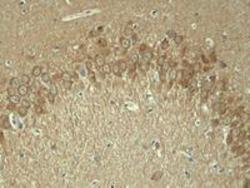

Supportive validation

- Submitted by

- GeneTex (provider)

- Main image

- Experimental details

- Immunohistochemical analysis of paraffin-embedded rat hippocampal region tissue from a model with Alzheimer¡¦s Disease using Tau (Phospho-Thr181) Antibody (GTX50171).